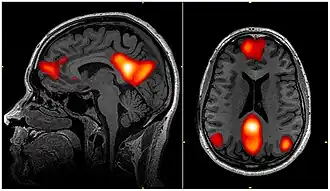

Imagem de fMRI mostrando regiões da rede de modo padrão

Na neurociência, a rede de modo padrão (DMN, do inglês Default Mode Network, ou RMP), também rede padrão, ou rede cerebral padrão, é uma rede cerebral de larga escala de regiões do cérebro em interação, conhecidas por terem atividade altamente correlacionada entre si e distinta de outras redes no cérebro.[3]

Foi inicialmente assumido que a rede de modo padrão estaria mais comumente ativa quando uma pessoa não está focada no mundo exterior e o cérebro está de repouso mas em vigília, como ao "sonhar acordado" e durante divagação mental. No entanto, agora se sabe que ela pode contribuir para elementos da experiência relacionados ao desempenho de tarefas externas.[4] Também é ativa quando o indivíduo está pensando nos outros, pensando em si mesmo, lembrando-se do passado e planejando o futuro.[3][5] Embora a DMN tenha sido originalmente observada como estando desativada em certas tarefas orientadas a objetivos e às vezes seja chamada de rede negativa à tarefa (task-negative),[6] ela pode estar ativa em outras tarefas orientadas a objetivos, como memória de trabalho social ou tarefas autobiográficas.[7] A DMN demonstrou estar correlacionada negativamente com outras redes no cérebro, como as redes de atenção.[8]